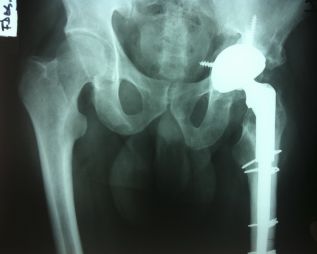

Ciudad de México. Igualar la longitud de las piernas en las personas con artroplastia de cadera puede resultar un tanto complicado, porque aunque existen varios métodos para hacerlo, no siempre funcionan perfectamente. Pese a que lo deseable es que después de la operación no haya diferencia en la longitud de ambas piernas, eso no siempre es posible y, en algunos casos, comenta el Dr. Richard Claridge,especialista en Cirugía Traumatológica y Ortopédica de Mayo Clinic,hasta puede ser necesaria una ligera diferencia entre ambas piernas para lograr la mejor estabilidad, a largo plazo, en la articulación de la cadera.